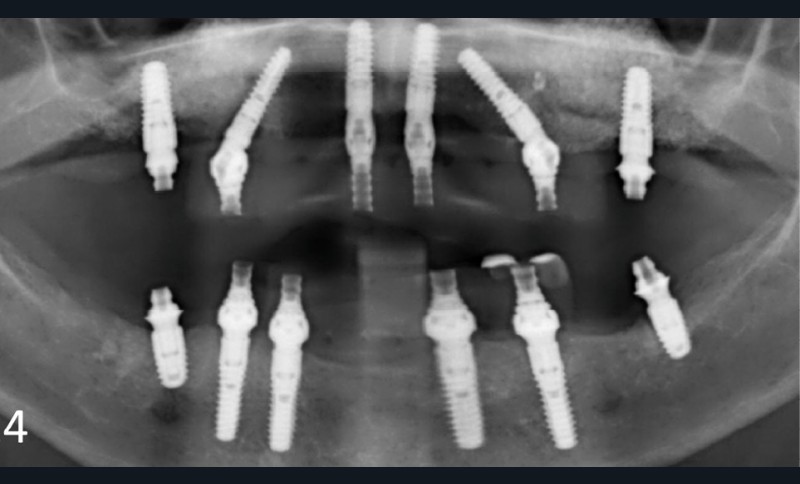

Une patiente ayant perdu ses incisives maxillaires à la suite d’un traumatisme quelques années auparavant, consulte en 2015 pour un inconfort occlusal persistant. Elle a été traitée par diverses gouttières occlusales, sans résultat notable. En 2017, une reconstruction globale est réalisée, toujours sans résolution de la plainte d’inconfort occlusal. Après avoir consulté de très nombreux praticiens et bénéficié de multiples traitements, en 2024 la patiente a perdu l’ensemble de ses dents ! En octobre 2025, après plusieurs prothèses globales sur implants, la plainte est toujours la même dans un contexte psycho-émotionnel de plus en plus difficile (fig. 1).